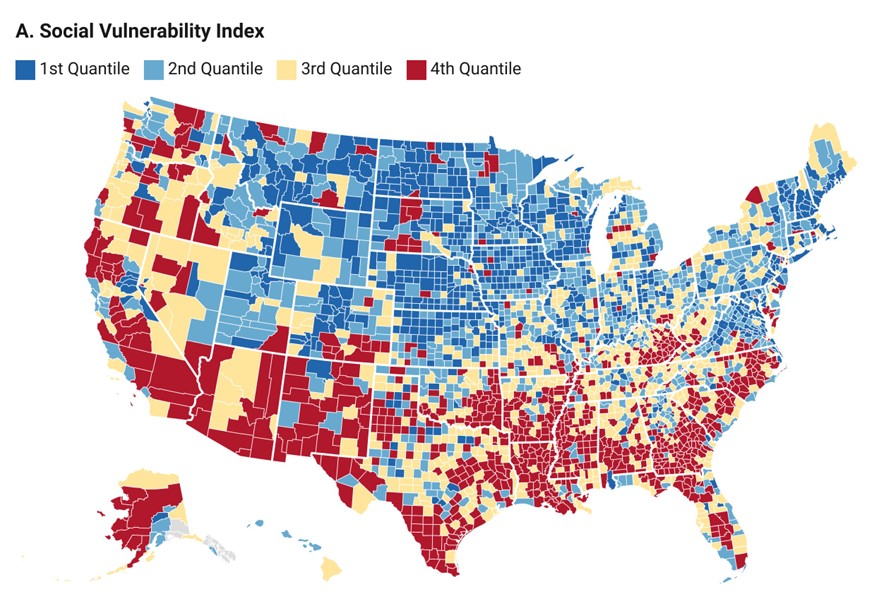

Disparities in premature heart failure mortality are driven by social vulnerability and race across U.S. counties Akshaya Bhagavathula ahajournals.org/doi/10.1161/CI… #AHAJournals